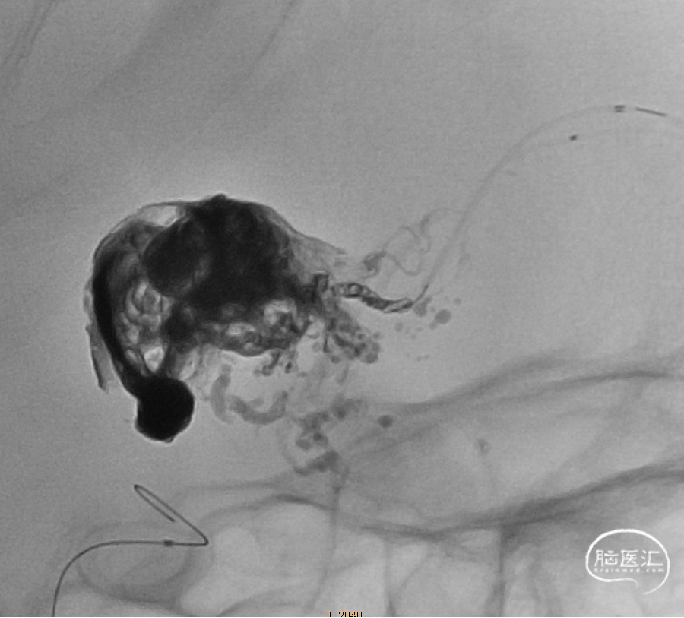

经Apllo微导管注入Onyx胶

术后造影脑动静脉畸形消失